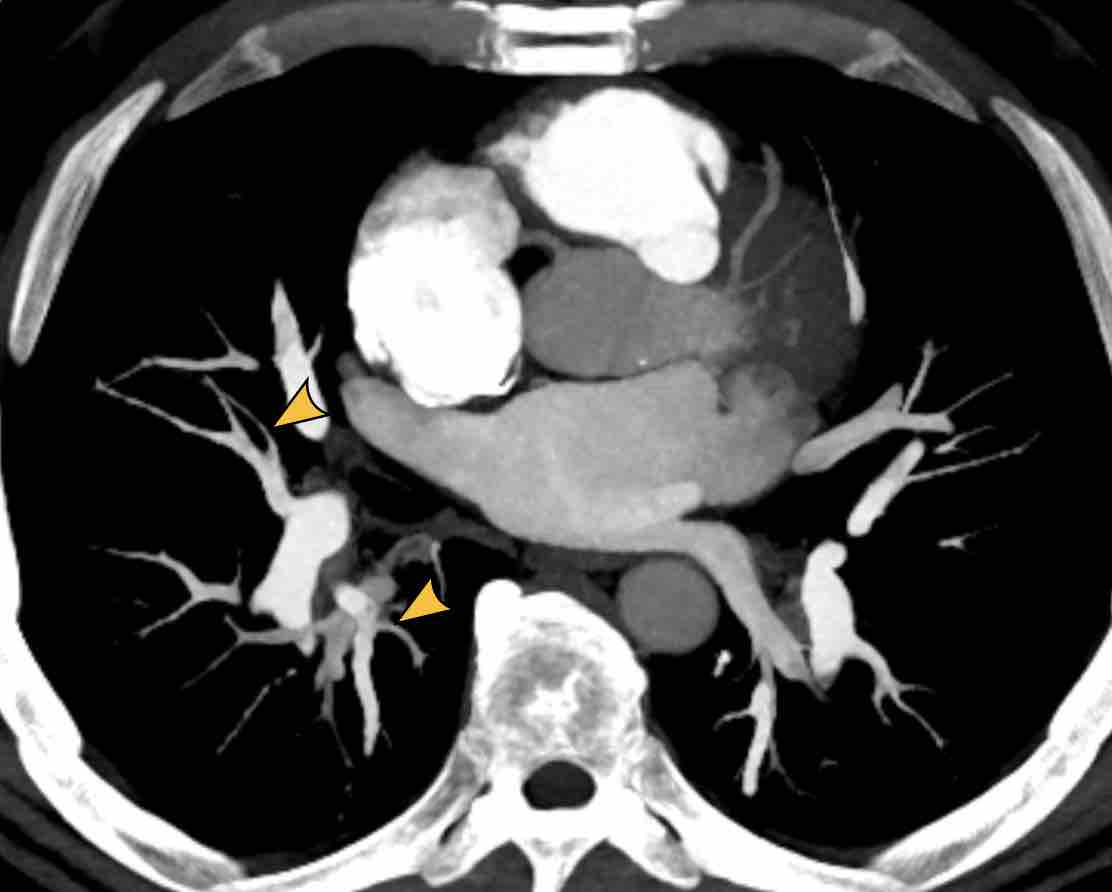

Thùy azygos ở nam giới 74 tuổi với tĩnh mạch azygos ở vị trí bình thường (mũi tên vàng).

Đây là một trường hợp khác, trong đó tĩnh mạch azygos đi qua rãnh liên thùy azygos (đầu mũi tên).